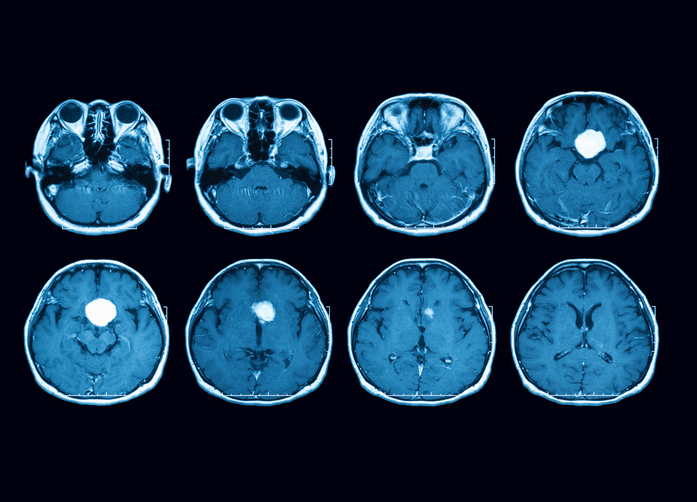

Endoscopic surgery is minimally-invasive, meaning it does usually not require a large incision. Neurosurgeons may make a small opening inside the nose to remove a growth through a thin lighted tube called an endoscope. An MRI is a type of picture taken of the skull base using magnets and a computer and may be done by a radiology specialist while the surgical specialists are operating to help them make sure all of the growth has been removed.